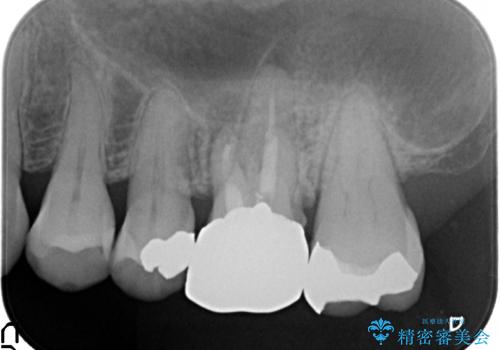

- 左上の奥歯にできものが出来てから口臭が気になるようになったので診て欲しいといらっしゃった方の症例です。

左上のできものは左上6の根尖病変が原因のフィステル(膿の出口)であったため、再根管治療を行いました。

フィステルの消失を確認後、オールセラミッククラウンによる補綴を行いました。